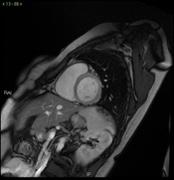

Le tecnologie avanzate che salvano la vita. Cardio RM senza e con contrasto: studiare le strutture cardiache con grande precisione